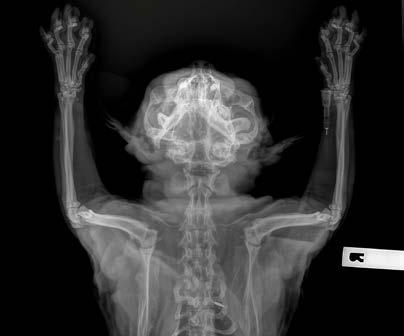

Bullet is a 7-year-old male Bull Arab x Border collie crossbreed. He was adopted by our client (who is one of our nurses) at 10-months-old. Castration was performed at 10-months-of-age through the rescue organisation, prior to the client adopting Bullet. Therefore, we are unsure if it was routine or cryptorchid castration. Bullet has previously been treated for heartworm infection but is currently up to date with all preventative care.

Bullet developed a mass where his scrotum would be if he were an entire male dog. The lump was noted during a bath, and was absent at vaccination two months prior. The lump remained stable for the two weeks between noticing the lump and removal. There were no other abnormalities noted at home or during physical examination.

An FNA of the lump was performed during consult. After consulting with Alinta, it was determined the FNA contained germinal epithelial cells. I could be forgiven for thinking the cells were possibly spindle cells, due to the morphology of a few singular cells, or agranular round cells. Germinal epithelial cells behave like epithelial cells forming cohesive clusters of cells, whereas spindle cells routinely do not. The granular cytoplasm of germinal epithelial cells could also be mistaken for mast cells.

A lumpectomy was performed the following week. The lumpectomy was essentially a scrotal ablation, with removal of the lump through the scrotal ablation site. Care was taken not to separate the lump from the surrounding tissue. The vas deferens was located, attached to the distal edge of the lump. The vas deferens and tunica were ligated as deep as possible. The lump was submitted for histopathology.

Sertoli Cell Tumour

With an absence of identifiable normal testicular tissue, the Sertoli cell tumour is likely to have arisen from a congenital or traumatic remnant of testicular tissue within the spermatic cord or scrotum. Thus, this case represents one of the rare circumstances in which this can occur and the challenges of diagnosing it as a primary clinician using in-house diagnostic techniques.

A case report of 17 castrated animals with sertoli cell tumours (Doxsee, A., Yager, J., Best, S., & Foster, R. (2006, August)) suggests ectopic testicular tissue, polyorchidism and transplantation of testicular tissue during castration as aetiologies. The median time to development of a Sertoli cell tumour was 8 years.